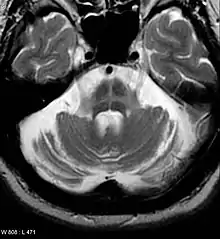

Imaging

Computed tomography (CT) scans of people with PD usually appear normal.[90] MRI has become more accurate in diagnosis of the disease over time, specifically through iron-sensitive T2* and SWI sequences at a magnetic field strength of at least 3T, both of which can demonstrate absence of the characteristic 'swallow tail' imaging pattern in the dorsolateral substantia nigra.[91] In a meta-analysis, absence of this pattern was highly sensitive and specific for the disease.[92] A 2020 meta-analysis found that neuromelanin-MRI had a favorable diagnostic performance in discriminating individuals with Parkinson's from healthy subjects.[93] Diffusion MRI has shown potential in distinguishing between PD and Parkinson-plus syndromes, though its diagnostic value is still under investigation.[90] CT and MRI are also used to rule out other diseases that can be secondary causes of parkinsonism, most commonly encephalitis and chronic ischemic insults, as well as less frequent entities such as basal ganglia tumors and hydrocephalus.[90]